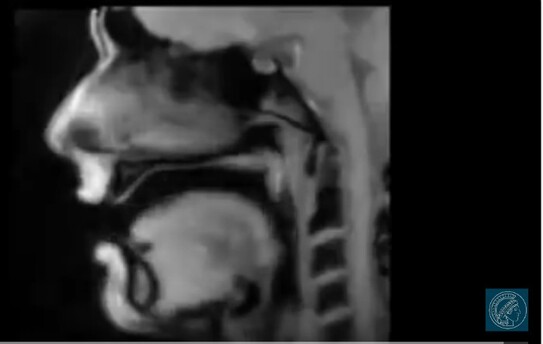

Tomografie prin rezonanţă magnetică (TRM) (Print screen YouTube)

În acest videoclip se vede imaginea din interior a unei persoane (germanul Dirk Voit) în timp ce vorbeşte. Atunci când pronunţă litera "r" partea din faţă a limbii vibrează, la litera "u" se îndoaie coloana vertebrală, când înghite, limba se aplatizează pe cerul gurii.

Imaginile detaliate (în timp real) au fost realizate datorită cercetării privind tomografia prin rezonanţă magnetică (TRM) de către Jens Frahm de la Max-Planck-Institut fur Biophysikalische Chemie din Gottingen, Germania.